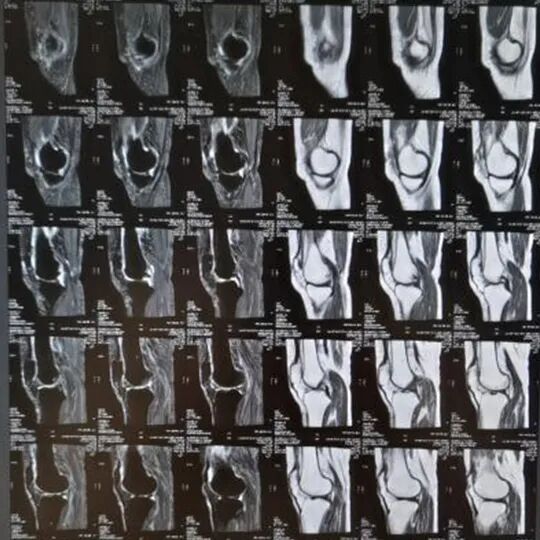

MR检查

它的优点是没有辐射,孕妇及婴幼儿均可以检查;其次,MR检查软组织分辨率高,是神经系统、生殖系统、关节及肌肉等软组织系统疾病诊断的首选检查,比如急性脑梗死、中枢神经系统病变、生殖系统病变、退行性骨关节病、软组织损伤及肿瘤等。它的缺点是:价格相对较贵,多用作其他检查的补充检查;检查时间较长,一般不作为急诊检查的首选方法;因为有磁场,对于体内外有铁磁性金属置入物的患者禁止使用;对于有幽闭恐惧症的人群也不适用。